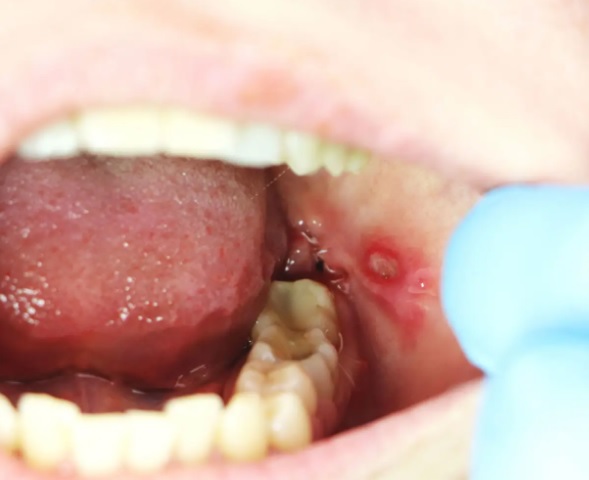

Afty to niewielkie, lecz wyjÄ…tkowo bolesne owrzodzenia pojawiajÄ…ce siÄ™ na bÅ‚onie Å›luzowej jamy ustnej, których nawracajÄ…cy charakter sprawia, że stajÄ… siÄ™ one problemem przewlekÅ‚ym i niezwykle trudnym do caÅ‚kowitego wyeliminowania. U wielu osób pojawienie siÄ™ aft wiąże siÄ™ z ostrym, piekÄ…cym bólem, uniemożliwiajÄ…cym normalne jedzenie, picie czy nawet mówienie, co bezpoÅ›rednio wpÅ‚ywa na codzienny komfort życia. Uciążliwość tej dolegliwoÅ›ci polega także na tym, że niekiedy afty pojawiajÄ… siÄ™ cyklicznie, powracajÄ…c nawet co kilka tygodni i stale przypominajÄ…c o swoim istnieniu. Z czasem mogÄ… prowadzić nie tylko do frustracji, ale nawet do obniżenia nastroju, a u osób zmagajÄ…cych siÄ™ z nimi latami – do przewlekÅ‚ego stresu i rezygnacji z ulubionych potraw. Dlatego tak ważne jest nie tylko leczenie samych zmian, np. poprzez miejscowe stosowanie preparatów takich jak maść na afty (zobacz wiÄ™cej: https://www.chema.rzeszow.pl/strefa-wiedzy/zel-aftident-sposob-na-afty-plesniawki-i-urazy-w-jamie-ustnej), ale także zrozumienie przyczyn ich nawrotów, by móc skutecznie ograniczyć ich wystÄ™powanie i poprawić jakość swojego życia.

Pochodzenie nawracajÄ…cych aft jest zÅ‚ożone i wielowymiarowe, a ich pojawianie siÄ™ może być efektem wspóÅ‚dziaÅ‚ania różnych czynników. KluczowÄ… rolÄ™ odgrywa tu stan odpornoÅ›ci organizmu – osÅ‚abienie ukÅ‚adu immunologicznego, wywoÅ‚ane przewlekÅ‚ym stresem, niedoborami witamin czy innymi schorzeniami, otwiera drogÄ™ bakteriom i wirusom do wnikania w bÅ‚onÄ™ Å›luzowÄ…. Zmiany hormonalne, zwÅ‚aszcza u kobiet w trakcie menstruacji, ciąży lub menopauzy, czÄ™sto prowadzÄ… do osÅ‚abienia mechanizmów obronnych Å›luzówki jamy ustnej i sprzyjajÄ… pojawianiu siÄ™ ran. Ogromne znaczenie ma także dieta – niedobór żelaza, witamin z grupy B, kwasu foliowego oraz witaminy C prowadzi do kruchoÅ›ci i Å‚atwej podatnoÅ›ci bÅ‚ony Å›luzowej na urazy. Dodatkowo, u osób z chorobami autoimmunologicznymi (np. zespóÅ‚ Behçeta czy celiakia), afty sÄ… jednym z objawów poważniejszych zaburzeÅ„ odpornoÅ›ci. Mechaniczne urazy, takie jak przygryzanie policzków czy nieprawidÅ‚owa technika szczotkowania, również mogÄ… inicjować proces powstawania aft. Zrozumienie tych mechanizmów jest niezbÄ™dne, by siÄ™gać po wÅ‚aÅ›ciwe dziaÅ‚ania, w tym systematyczne korzystanie z preparatów takich jak maść na afty, które nie tylko Å‚agodzÄ… ból, ale wspierajÄ… regeneracjÄ™ i ograniczajÄ… rozwój nowych zmian.